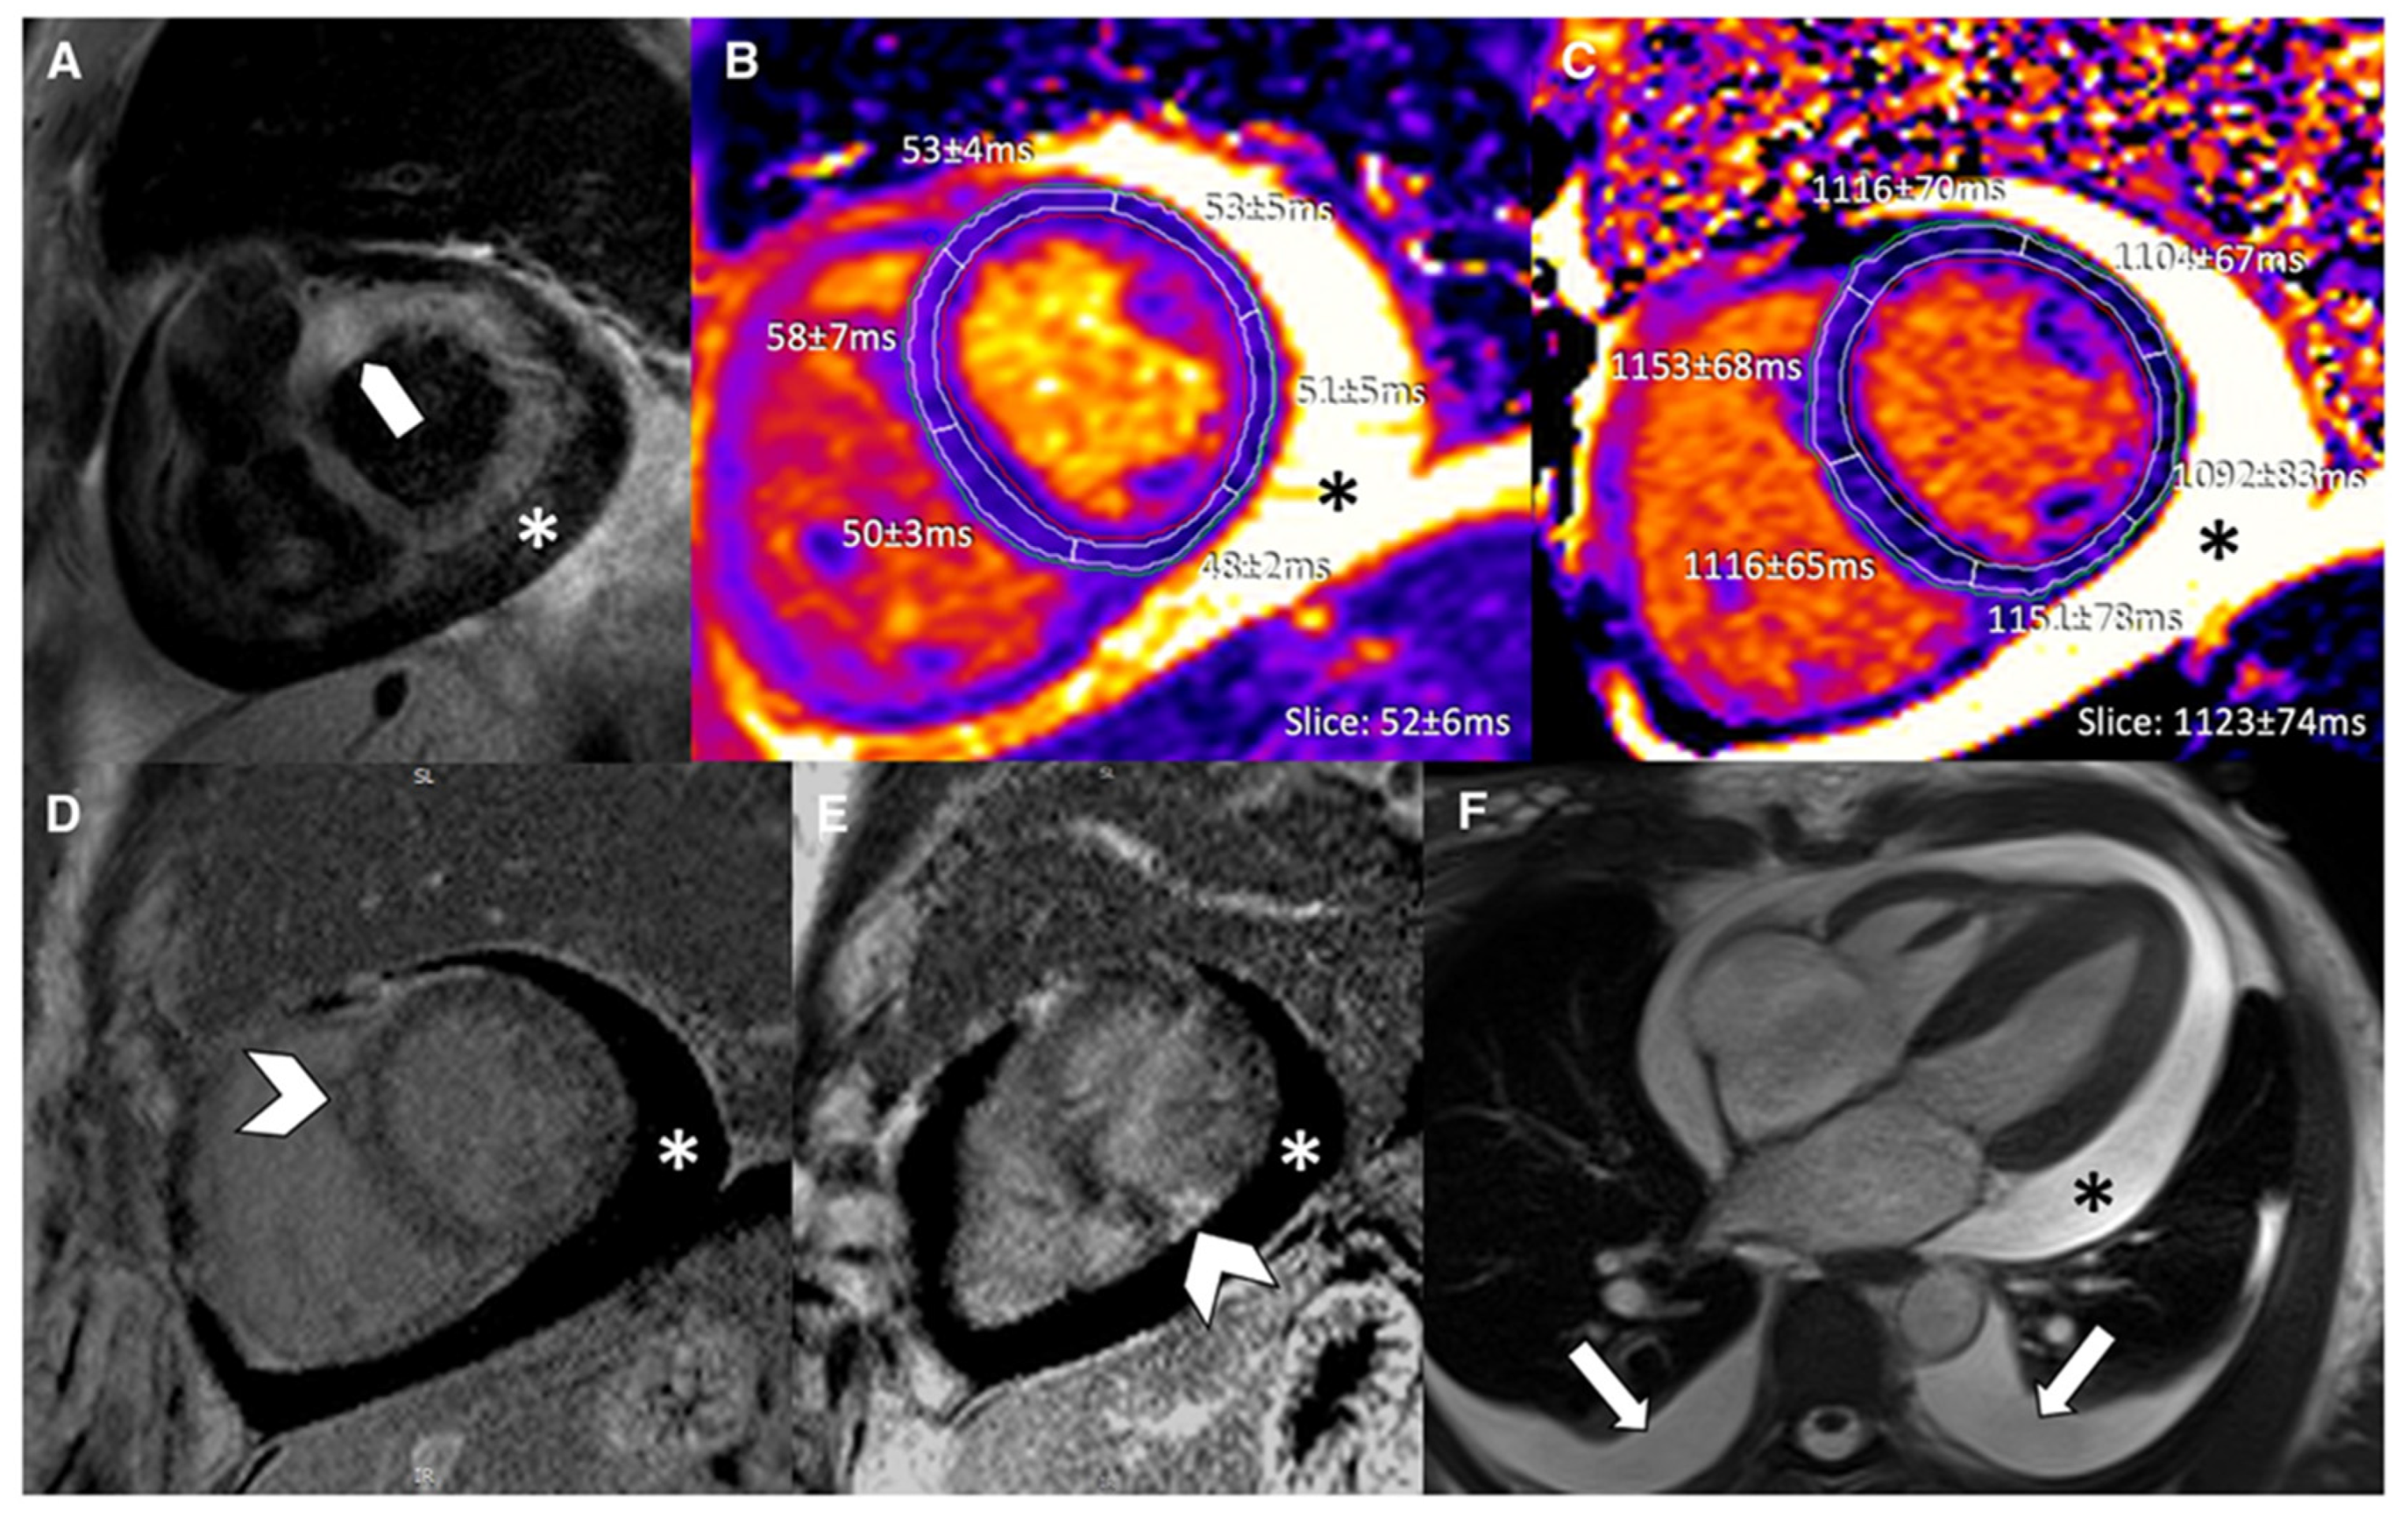

Natural course of myocarditis as seen by cardiovascular magnetic resonance using quantitative techniques and late gadolinium enhancement.

- Acute Myocarditis: This initial stage, typically lasting less than a month, is characterized by active myocardial inflammation. Pathologically, this involves myocyte injury either directly by the inciting agent (e.g., virus) or indirectly by the triggered immune response, leading to intracellular edema, hyperemia, and early necrosis [5]. Clinically, patients may present with chest pain, heart failure symptoms, or arrhythmias. CMR at this stage typically shows myocardial edema, early gadolinium enhancement (EGE), and late gadolinium enhancement (LGE) [6] (Figure 3). From a biochemical standpoint, acute myocarditis is typically accompanied by elevation of myocardial necrosis markers, predominantly cardiac troponins, which reflect the extent of myocyte injury but only moderately correlate with CMR tissue damage [7,8,9]. In a cohort of patients with acute myocarditis, peak cardiac troponin T showed a linear association with total LGE volume (R2 ≈ 0.57, p < 0.001), whereas no significant correlation was found with the T2 signal intensity ratio, underscoring that LGE is a better marker of irreversible injury than edema. Conversely, another study reported that the proportion of LGE-positive myocardium did not correlate with the amount of necrosis estimated from troponin T release, highlighting the imperfect relationship between focal scar on CMR and global biochemical injury. Overall, troponin elevation supports the diagnosis in the acute phase, but CMR—through LGE and mapping—more accurately characterizes the pattern and extent of myocardial involvement.

Figure 3. Appearance of acute and subacute myocarditis in CMR. (A) Changes are more pronounced in acute myocarditis, as demonstrated by high prevalence and extent of late gadolinium enhancement (LGE) and elevated T2. (B) Subacute myocarditis can show increased LGE as well as elevated T1, ECV, and T2, but in many cases, changes are subtle. Reproduced from: Brendel, J.M., et al. (2022) [6]. Licensed under CC BY 4.0. (https://creativecommons.org/licenses/by/4.0/ accessed on 15 December 2025). - Subacute Myocarditis: This is a transitional phase (duration of symptoms > 4 weeks to <3 months) where the acute inflammatory response begins to subside. There may be a mix of persistent edema and the early establishment of repair processes, including the beginning of fibrotic scar formation. In the subacute phase, serum troponin and inflammatory markers usually decline or normalize, while CMR often still demonstrates residual abnormalities, indicating a temporal dissociation between enzymes and imaging [6,9]. Follow-up CMR studies in patients approximately 3 months after an acute episode have shown persistent LGE or increased native T1/ECV in a significant proportion of cases despite normalization of cardiac enzymes and CRP, reflecting ongoing structural remodeling rather than active myocyte necrosis. In one series, CMR frequently revealed persistent disease activity at 3-month follow-up even though cardiac enzymes and inflammatory parameters had returned to normal, emphasizing that multiparametric CMR is more sensitive than circulating biomarkers for detecting subacute myocardial injury.

- Chronic Myocarditis: With persistent inflammation and symptoms lasting more than 3 months, this stage can lead to a chronic inflammatory cardiomyopathy [3]. The ongoing inflammation, usually driven by autoimmune mechanisms, results in progressive myocardial damage, diffuse interstitial fibrosis, and systolic dysfunction. CMR may show persistent or fluctuating edema on T2-weighted sequences alongside LGE [10] (Figure 4). In chronic myocarditis and inflammatory cardiomyopathy, classical myocardial enzymes are often normal or only mildly elevated, and their correlation with CMR findings becomes weak. Patients may exhibit persistent non-ischemic LGE and diffusely increased native T1 and ECV—reflecting fibrosis and low-grade inflammation—despite normal troponin and CK levels, indicating that tissue characterization by CMR is more informative than enzymes for assessing ongoing disease activity in this stage. Conversely, systemic inflammatory markers such as CRP or ESR can be variably elevated and show only a loose relationship with mapping or LGE burden, so current evidence supports using CMR (and, when appropriate, PET) as the reference non-invasive tool to monitor chronic inflammation and remodeling, while serum biomarkers play a complementary role [9,10,11,12].

Figure 4. Typical CMR findings of chronic healed myocarditis and DCM. T2w and T2 mapping show marked edema in chronic myocarditis contrary to healed myocarditis and DCM. Increased T1 relaxation times and ECV were present in all groups, prominently depicted in the chronic myocarditis and DCM examples. Reproduced from: Krumm, P., et al. (2022) [10]. Licensed under CC BY 4.0. (https://creativecommons.org/licenses/by/4.0/, accessed on 15 December 2025). - Resolved Myocarditis: In many cases, particularly viral, the inflammation resolves completely without significant sequelae. Follow-up CMR may show complete normalization of T1, T2, and increased extracellular volume (ECV) values and the absence of new LGE.